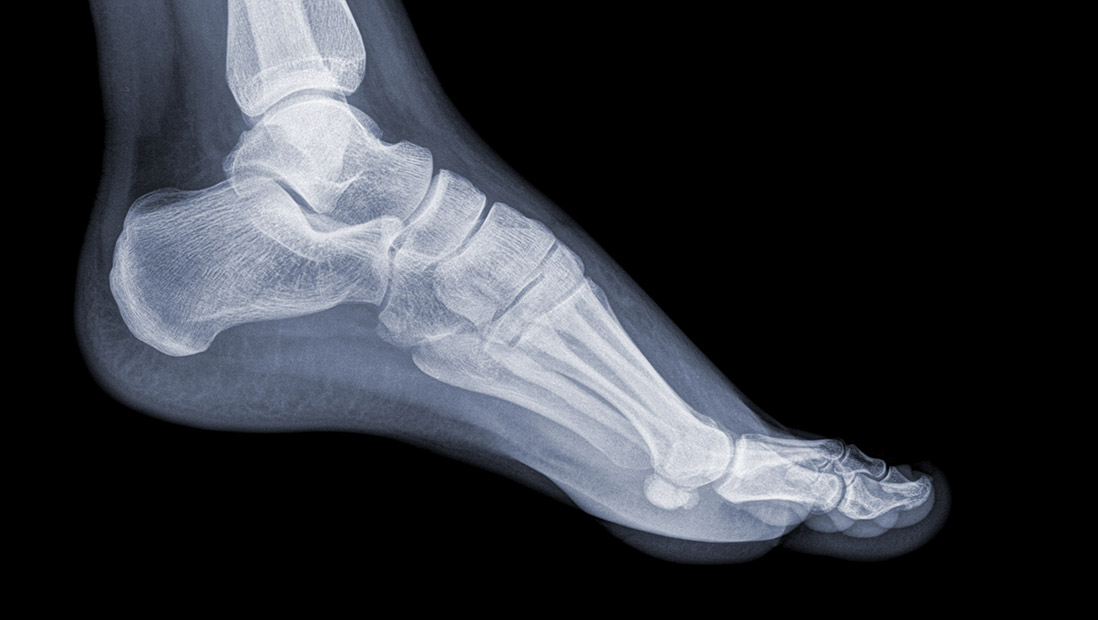

Pathologies affectant le pied ou la cheville

Il existe de nombreuses pathologies affectant le pied ou la cheville et il est utile de s’informer sur celles-ci afin de comprendre votre problème et d’en avertir le médecin le plus efficacement possible. Le Dr. Michèle Bertrand, chirurgienne orthopédique à Tournai et à Mouscron, vous renseigne en la matière.

Pathologies du pied ou de la cheville les plus courantes

Sur les documents ci dessous , vous pouvez cliquez sur la zone de votre pied qui est douloureuse et qui correspond soit à la cheville , l'arrière pied, la plante du pied , le médio-pied et l'avant-pied

Vous retrouverez une descriptions des problèmes les plus fréquents retrouvés à cet endroit et de leur prise en charge .